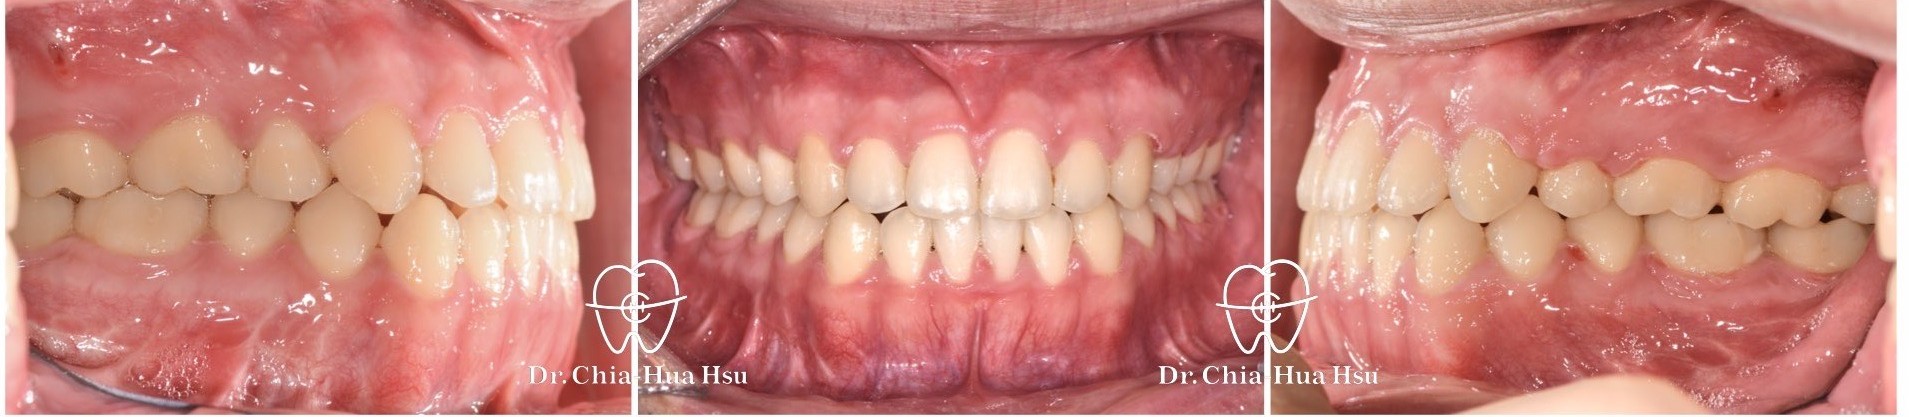

戽斗、開咬、齒列不正

成⼈矯正 | ⾦屬矯正 | 正顎⼿術 | 拔牙治療

• 20多歲的日籍大學生小時候有做過矯正治療,不過下顎骨隨著年紀持續生長,變成戽斗且開咬的樣子。於是,患者接受了矯正合併正顎手術,不但改善外觀,也改善了咬合功能與牙齒排列(患者很開心可以咬斷麵條)。

• 病患主訴:戽斗、前牙開咬。

• 問題分析:患者是標準的骨骼三類咬合(Skeletal Class III),下巴明顯較長,還有上顎牙弓過窄、開咬以及齒列不正。

• 治療方式:使用傳統金屬矯正器,合併正顎手術(雙顎),上顎拔除兩顆小臼齒以利手術方式進行上顎牙弓擴寬。

• 治療時間:1 年 7 個月。

• 治療結果:齒列排齊,咬合功能恢復,外觀更和諧。

治療前

治療後